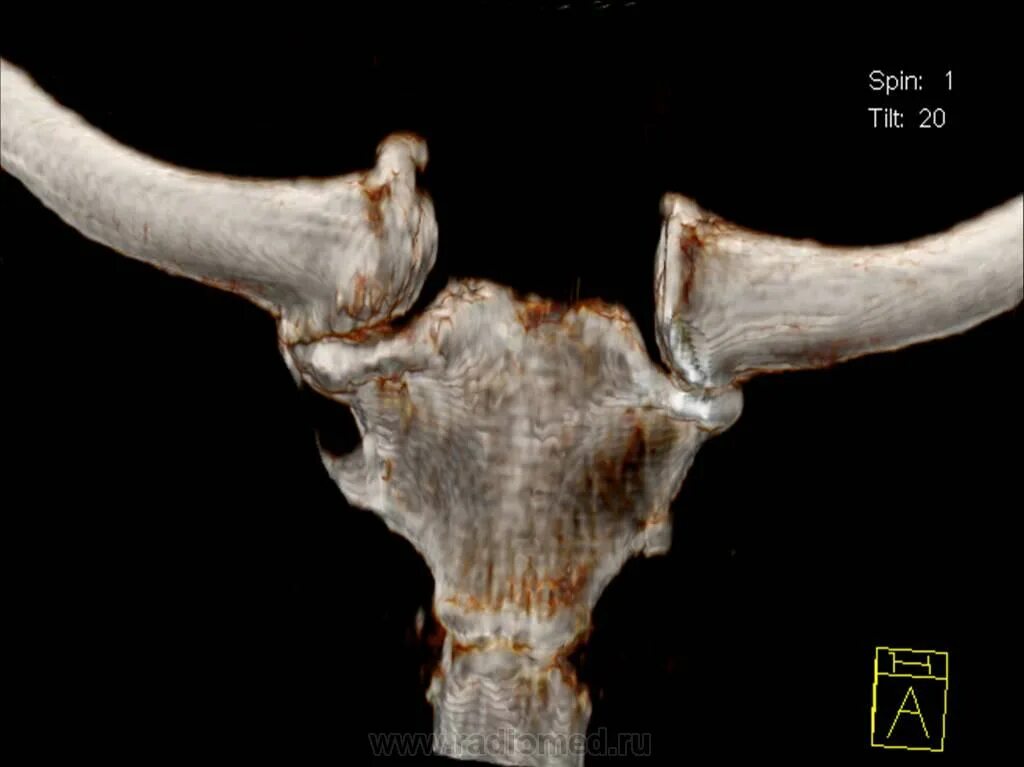

Грудино ключичная артрит